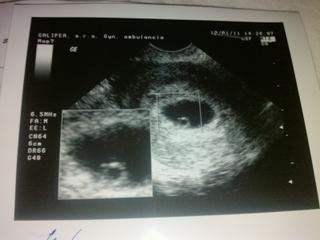

@0snezenka0 takto sono u mna vyzeralo v 6 tt - na konci 6 tt..tiez je tam iba vacok